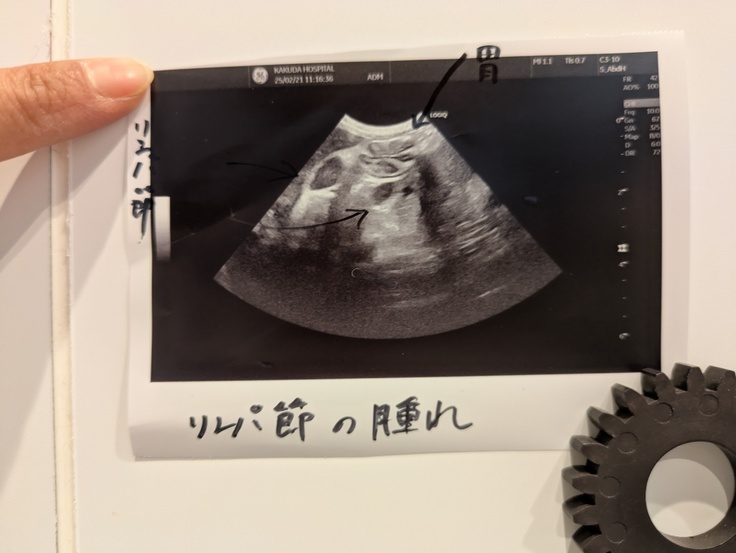

私は喉や腸になにかがあるんじゃないかと疑っていましたがエコーの結果リンパ節が腫れていることが分かりました。